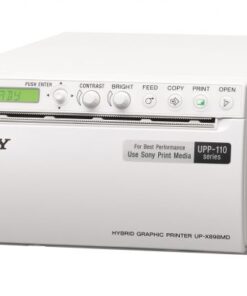

| USB,VGA,VIDO Print port | |

Real photos